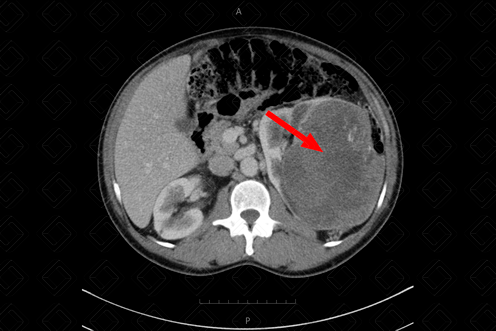

Descrição da figura : Tomografia computadorizada do abdome, estudo pós-contraste, fase portal evidenciando lesão hipovascular, heterogênea, no terço superior do rim esquerdo (seta vermelha).

• Tomografia computadorizada do abdome: Sempre seve ser realizado após a administração do contraste venoso, contendo as fases portal e excretora (tardia). Lesões com forte impregnação pelo meio de contraste, em geral, serão ou carcinoma de células renais (subtipo células claras) ou oncocitoma ou angiomiolipoma pobre em gordura (f igura acima);